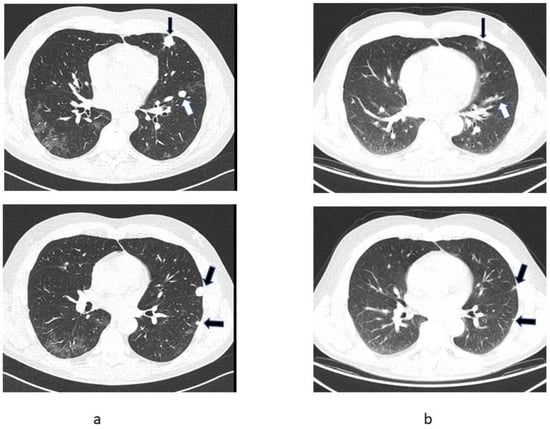

2.1. Patient 1

2.2. Patient 2